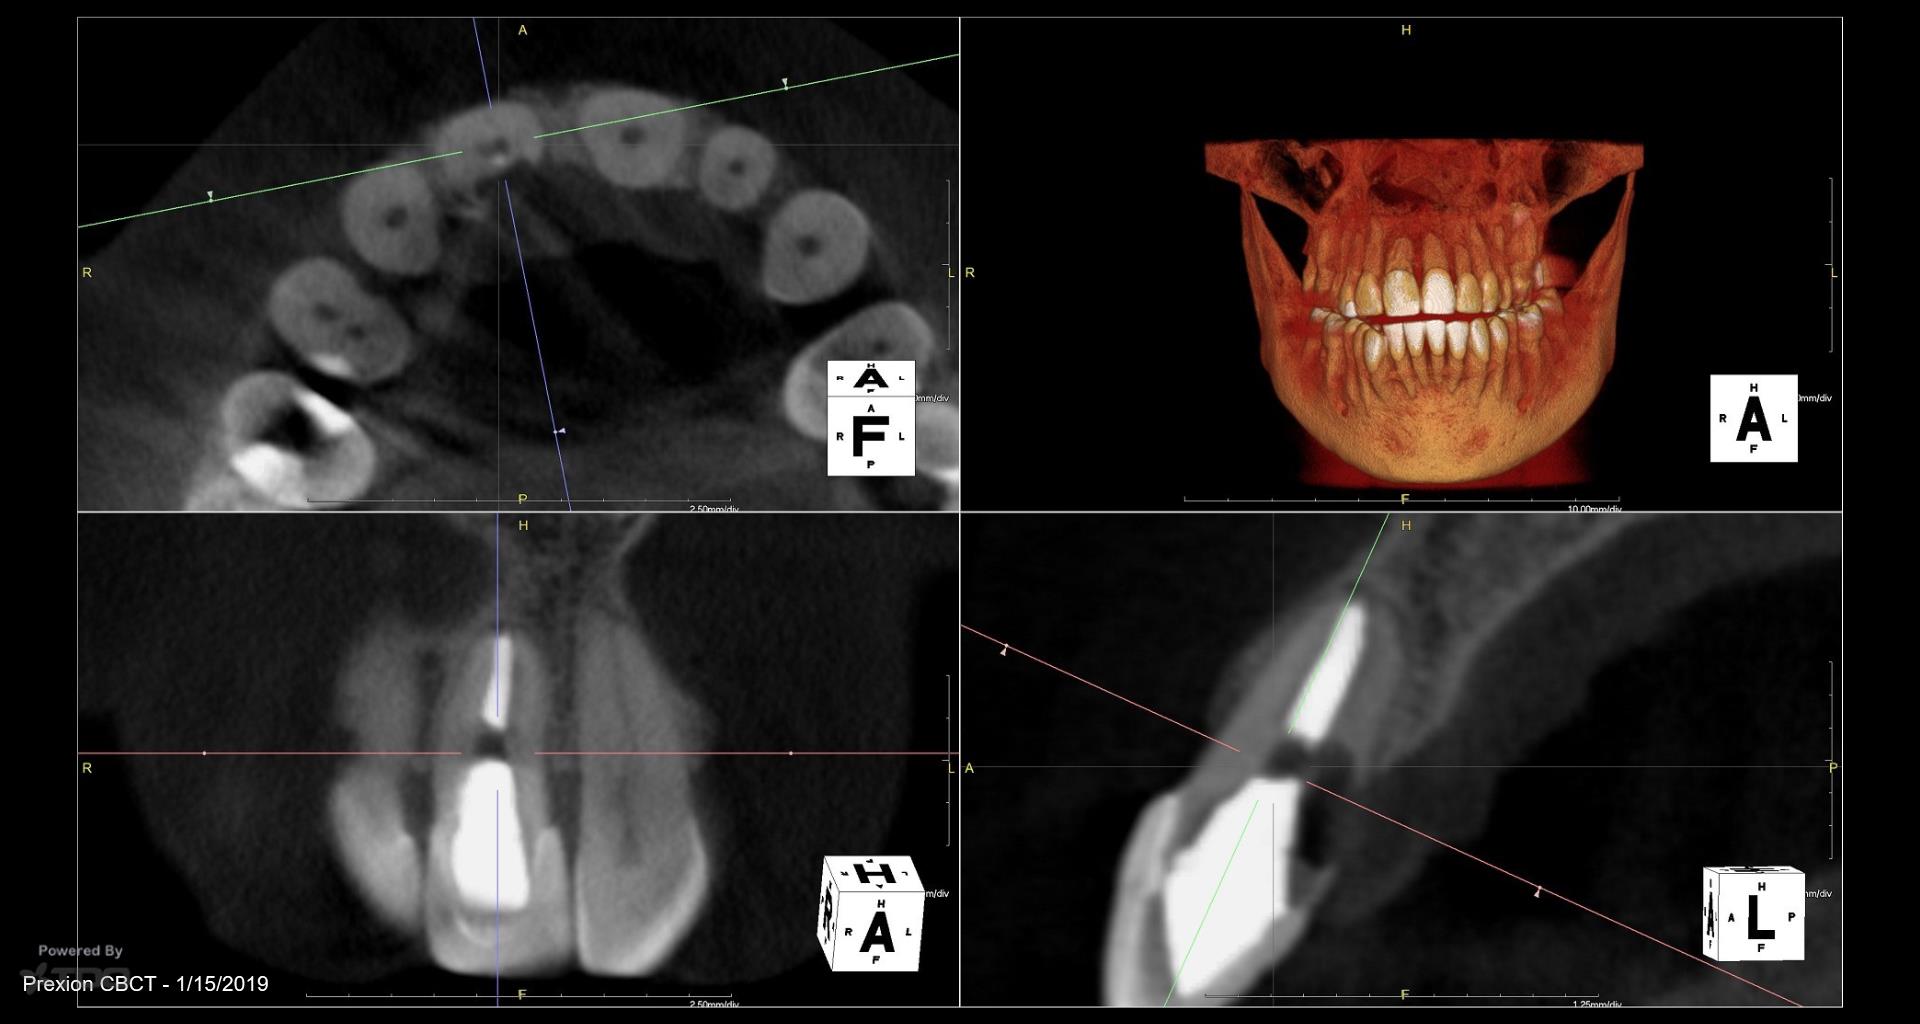

I did this RCT 34 years ago when the patient was 14. Now there is a parulis and lingual palpation sensitivity. Extract or treat? Patient has a very high smile line, thin biotype, is sensitive to costs. gbc

What is the treatment option being considered? Can you flap and repair? The lesion appears well-demarcated, without bone ingrowth, so it may be a simple repair with minimal ostectomy. If the patient can tolerate a couple black triangles (despite only flapping the palatal), then I might do it.